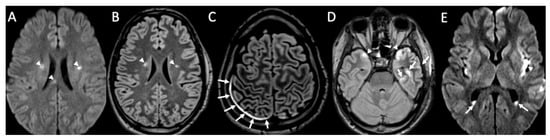

| Piogenic Meningitis | • Cerebrospinal fluid hyperintensity in T1 and FLAIR • Restricted diffusion of the subarachnoid spaces • Meningeal enhancement on T1 and FLAIR |

| Tuberculosis | • Leptomeningeal enhancement in the basal cisterns • Hydrocephalus very common • Infarcts in the basal ganglia due to vasculitis • Possible concomitant tuberculomas or miliary tuberculosis |

| Cryptococcus Neoformans | • Leptomeningeal enhancement • Cryptococcoma • Gelatinous pseudocysts |

| Candida albicans | • Microabscesses • Vascular lesions |

| Aspergillus fumigatus | • Abscesses • Vascular lesions |

| Herpes Virus type 1 | • Mesio-temporal involvement • Bilateral and asymmetric pattern • Cortical hyperintensity on T2 and FLAIR, with restricted diffusion (acute phase) and cortical enhancement (subacute phase) • Hemorrhagic foci |

| Varicella Zoster Virus | • Leptomeningeal enhancement • Cerebellitis |

| Cytomegalovirus | • Hyperintense areas in T2 and FLAIR in the periventricular white matter • Ventriculitis |

| Human herpesvirus type 6 | • Similar to herpes virus type 1, but cortical enhancement is more common |

| West Nile virus | • Hyperintensity in T2 and FLAIR of basal ganglia, thalami and midbrain |

| Enterovirus | • Rhombencephalitis |